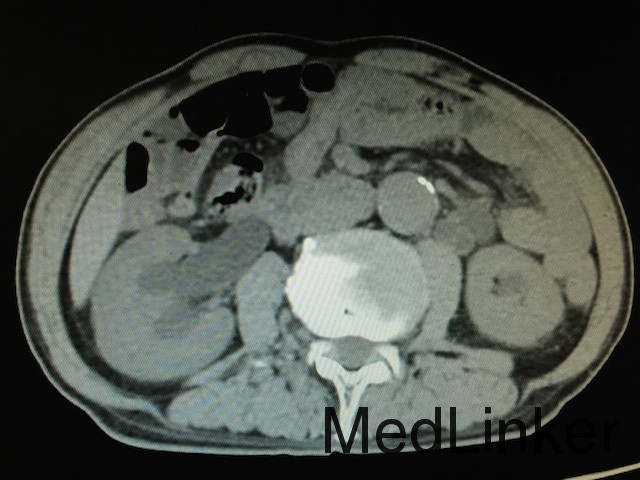

查体:无明显异常。 辅助检查:泌尿系CT(如下图所示):膀胱实性占位,增强扫描肿物呈不均匀强化,双侧输尿管及肾盂积水,结合患者既往史,考虑膀胱恶性肿瘤复发;骨扫描未提示骨转移灶;胸片无明显异常。

诊断:膀胱恶性肿瘤复发、双肾积水、膀胱憩室 治疗:建议行膀胱癌根治术+尿路转流术,患者家属拒绝,故行膀胱镜探查及双侧输尿管支架植入术改善双肾积水,改善肾功能。